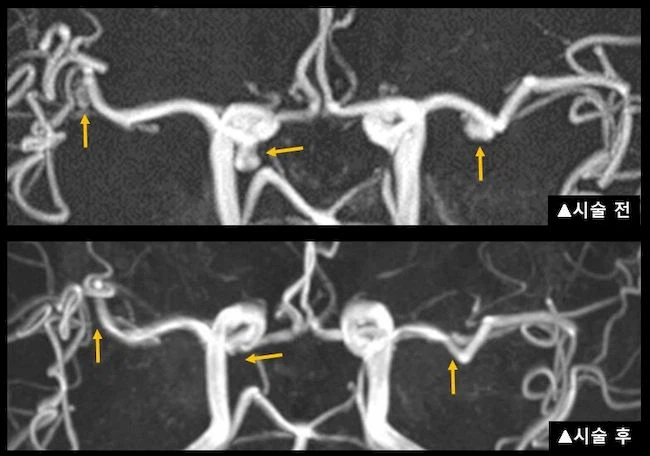

뇌동맥류의 치료는 동맥류의 출혈을 막는 것이 주된 목적입니다. 치료 방법으로는 머리를 열고 수술하는 뇌동맥류 결찰술(클립)과 혈관내 수술을 통해 백금코일을 동맥류내강에 삽입하는 뇌동맥류 색전술(코일)이 있습니다. 환자의 연령, 전신 상태, 동맥류의 위치, 크기, 모양 등에 따라 수술방법 및 시기를 결정하게 됩니다.

뇌동맥류 결찰술(클립)과 뇌동맥류 색전술(코일)의 종류는 모양과 길이, 기능에 따라 매우 다양하며, 최근에는 이 두 가지 치료법을 복합적으로 사용하여 보다 완벽하게 뇌동맥류를 치료하고 있습니다. 하지만 항상 뇌동맥류의 치료는 항상 위험성이 따르므로 치료의 선택에 신중을 기해야 합니다.